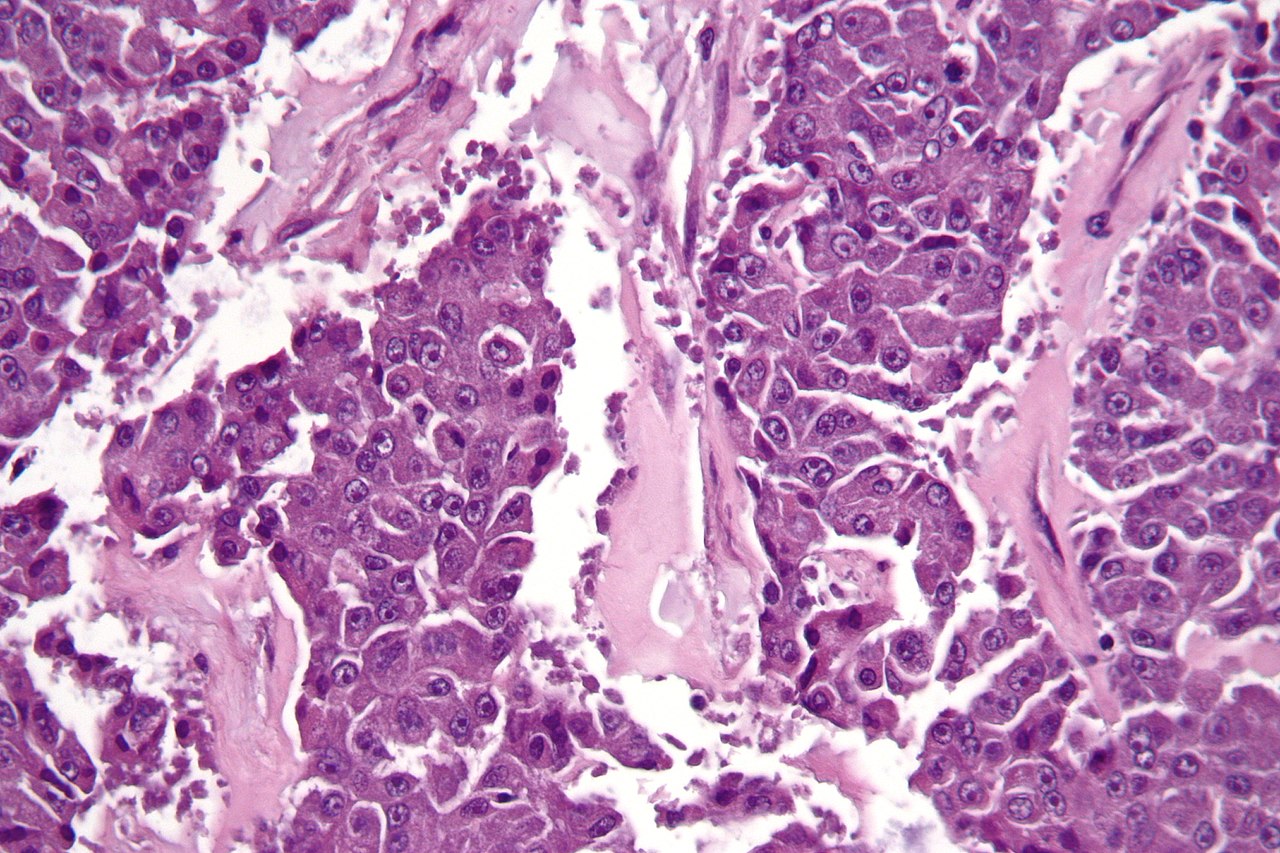

Los inhibidores de PARP, como el Olaparib, bloquean uno de los sistemas que usan las células para reparar su ADN. Están diseñados para atacar tumores que ya no son capaces de reparar su ADN, especialmente en los cánceres de ovario y de mama en mujeres con mutaciones en los genes supresores de tumores BRCA1 y BRCA2.

Los investigadores analizaron tumores de pacientes con diferentes tipos de cáncer y descubrieron que aquellos con deficiencias en la reparación de su ADN contenían significativamente más células inmunitarias, en comparación con los tumores en pacientes con un sistema de reparación de ADN en funcionamiento. Esto sugiere que las mutaciones de reparación del ADN estaban estimulando una respuesta inmune contra los tumores.

Cuando las células cancerosas con sistemas de reparación defectuosos se tratan con inhibidores de PARP para bloquear el sistema restante de reparación del ADN, ya no pueden reparar ningún daño en su material genético, por lo que acumulan cada vez más mutaciones del ADN hasta que mueren.